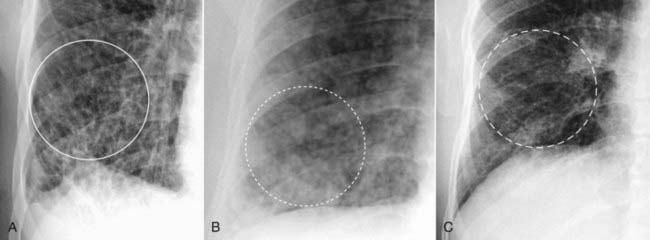

Figure 3-8 The patterns of interstitial lung disease.

A, The disease is primarily reticular in nature, consisting of crisscrossing lines (solid white circle). This patient had advanced sarcoidosis. B, The disease is predominantly nodular (dotted white circle). The patient was known to have thyroid carcinoma, and these nodules represent innumerable small metastatic foci in the lungs. C, Interstitial disease of the lung, reticulonodular. Most interstitial diseases of the lung have a mixture of both a reticular (lines) and nodular (dots) pattern, as does this case, which is a close-up view of the right lower lobe in another patient with sarcoidosis. The disease (dashed white circle) consists of both an intersecting, lacy network of lines and small nodules.

These “particles” of disease can be further characterized as having three patterns of presentation:

image Reticular interstitial disease appears as a network of lines (see Fig. 3-8A).

image Nodular interstitial disease appears as an assortment of dots (see Fig. 3-8B).

image Reticulonodular interstitial disease contains both lines and dots (see Fig. 3-8C).